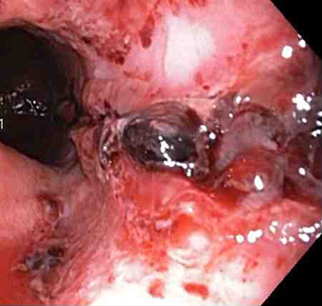

Nonbleeding adherent clot

From the collection of Juan Carlos Munoz, MD, University of Florida